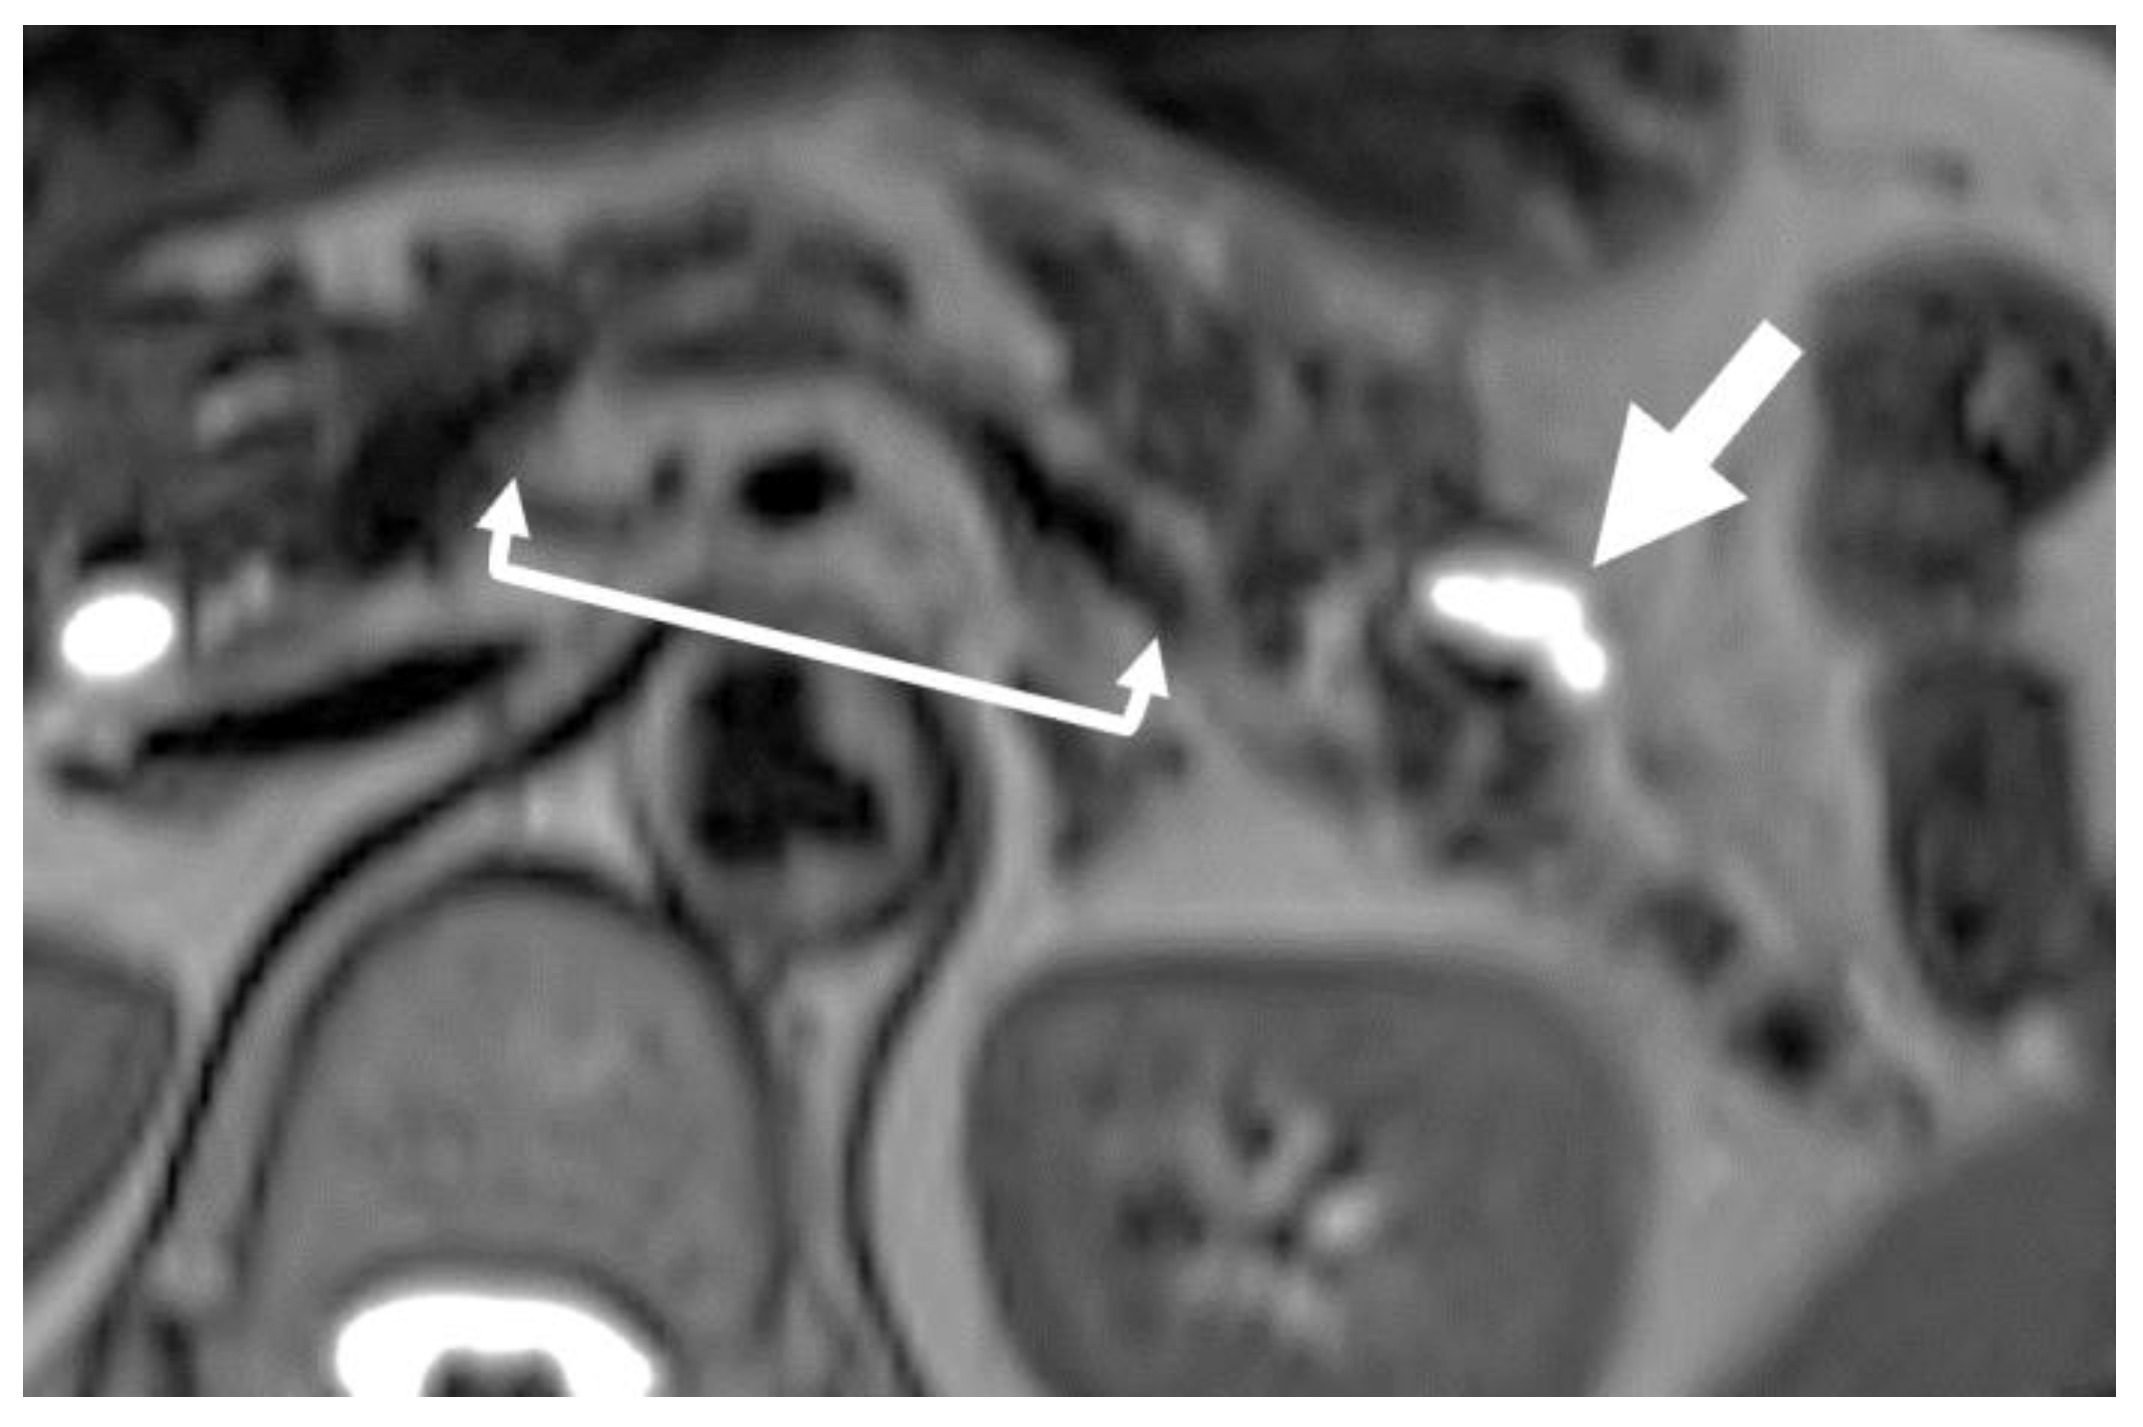

- Nakahodo, J.; Kikuyama, M.; Nojiri, S.; Chiba, K.; Yoshimoto, K.; Kamisawa, T.; Horiguchi, S.I.; Honda, G. Focal Parenchymal Atrophy of Pancreas: An Important Sign of Underlying High-Grade Pancreatic Intraepithelial Neoplasia without Invasive Carcinoma, i.e., Carcinoma in Situ. Pancreatology 2020, 20, 1689–1697. [Google Scholar] [CrossRef] [PubMed]

- Kikuyama, M.; Nakahodo, J.; Honda, G.; Horiguchi, S.; Suzuki, M.; Chiba, K.; Tabata, H.; Ome, Y.; Kamisawa, T. Effectiveness of Focal Pancreatic Parenchymal Atrophy in Diagnosing High-Grade Pancreatic Intraepithelial Neoplasia/Carcinoma In Situ. MRAJ 2021, 9, 8. [Google Scholar] [CrossRef]

- Nakahodo, J.; Kikuyama, M.; Fukumura, Y.; Horiguchi, S.I.; Chiba, K.; Tabata, H.; Suzuki, M.; Kamisawa, T. Focal Pancreatic Parenchyma Atrophy Is a Harbinger of Pancreatic Cancer and a Clue to the Intraductal Spreading Subtype. Pancreatology 2022, 22, 1148–1158. [Google Scholar] [CrossRef]

- Toshima, F.; Watanabe, R.; Inoue, D.; Yoneda, N.; Yamamoto, T.; Sasahira, N.; Sasaki, T.; Matsuyama, M.; Minehiro, K.; Tateishi, U.; et al. CT Abnormalities of the Pancreas Associated with the Subsequent Diagnosis of Clinical Stage I Pancreatic Ductal Adenocarcinoma More Than 1 Year Later: A Case-Control Study. AJR 2021, 217, 1353–1364. [Google Scholar] [CrossRef]